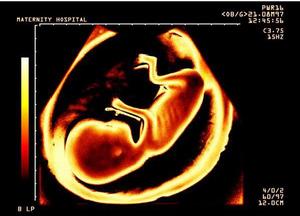

胎兒本病一般預後良好繼發性紅熱肢痛症以治療原發病為主經治療可以緩解但可能復發。